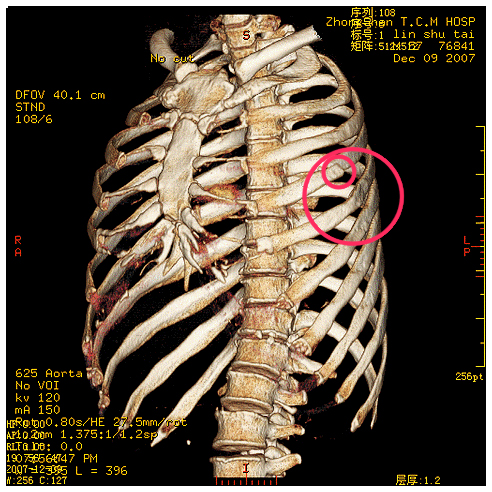

16层螺旋ct多种重建方法在诊断肋软骨骨折中的应用 罕见病 疑难病 会诊平台 专家会诊 网上会诊 医学影像

16层螺旋ct多种重建方法在诊断肋软骨骨折中的应用 罕见病 疑难病 会诊平台 专家会诊 网上会诊 医学影像

16层螺旋ct多种重建方法在诊断肋软骨骨折中的应用 罕见病 疑难病 会诊平台 专家会诊 网上会诊 医学影像